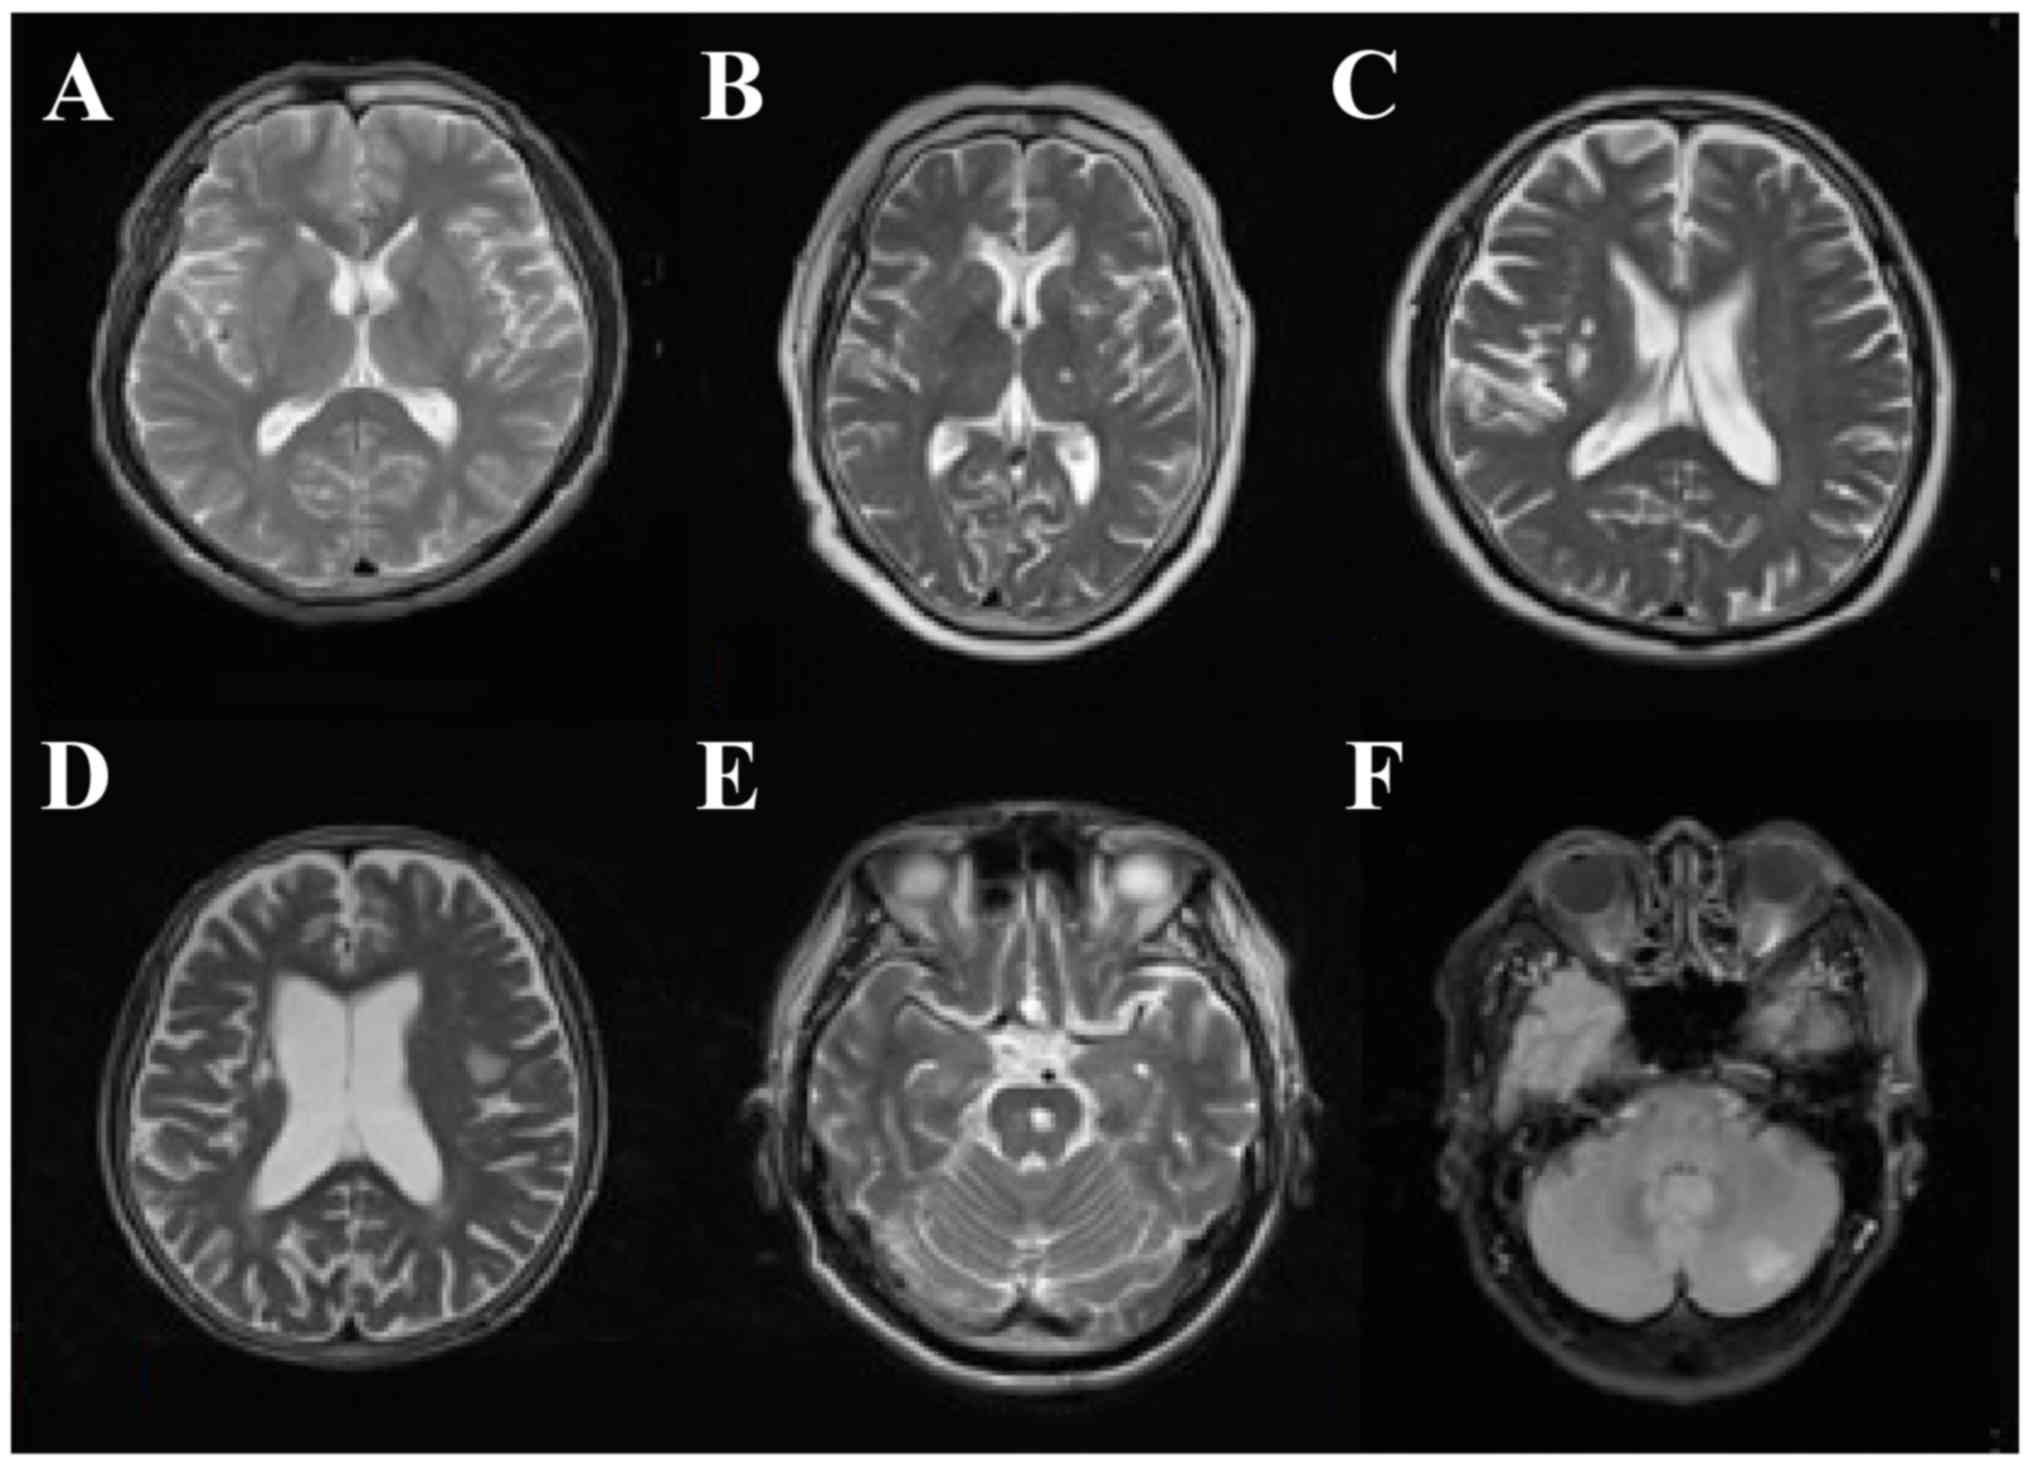

The infarction foci of DN patients with SCI presented as different sizes and shapes. Among SCI patients, 30 patients had lacunar infarction (diameter ≤20 mm), 22 had a single lesion and 28 had multiple lesions. The infarction foci of 28 patients were identified in the basal ganglia region and others were evident in the internal capsule, ventricle, thalamus, left temporal lobe, radial crown, bridge brain and insular lobe. Generally, SCI patients had no focal neurological signs. Non-specific signs included headache, dizziness, fatigue, impaired memory, slow response and subjective feeling and limb numbness (Fig. 1).

Figure 1.

MRI features in diabetic nephropathy patients complicated with silent cerebral infarction. (A) Normal control, (B) multiple lacunar infarction, (C) right basal ganglia region infarction, (D) left temporal lobe and insular lobe infarction, (E) pontine infarction, and (F) left cerebellar infarction.